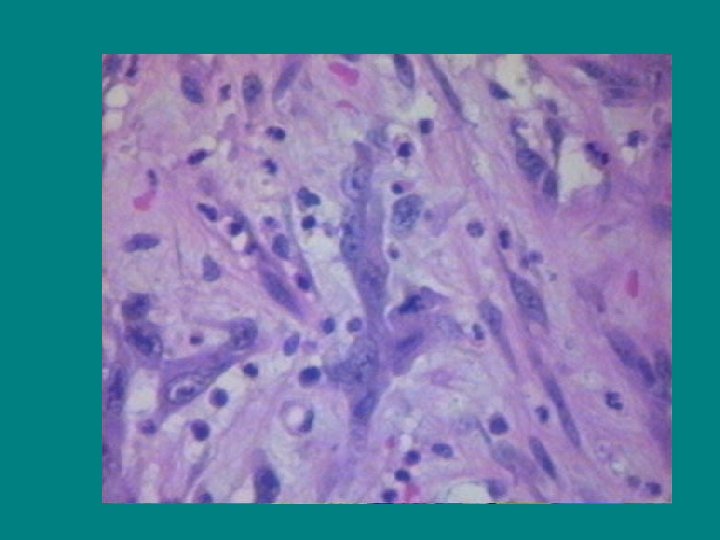

OMOGET TERATOM